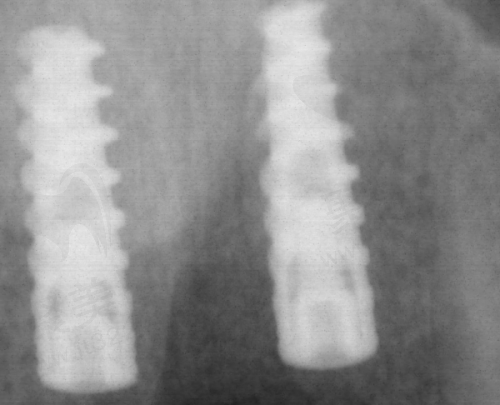

种植体品牌对价格影响较大。进口高端品牌,像瑞士、德国的,技术成熟、稳定性高,价格普遍在 12000 - 20000 元。比如说瑞士 ITI 种植体,它就属于高端品牌,在三亚的价格大概在 15000 - 20000 元。这是因为它采用了精良的材料和工艺,生物相容性好,能和牙槽骨更好地融合,就像一把合适的钥匙能精细开锁一样,适合骨条件较差的人。

韩国或国产中端品牌性价比更高,价格约为 5000 - 10000 元。韩国登腾种植体,价格在 5500 - 7000 元,它的适应症比较广泛,特别多人都适用。国产的百康特种植体,价格在 3000 - 4500 元,虽然价格相对较低,但基础功能也能达标,适合预算有限的朋友。

1. 瑞士/德国高端品牌

价格范围在 15000 - 20000 元。特点是长期稳定性强,适合骨条件较差者。就像前面说的瑞士 ITI 种植体,它的表面处理技术特别精良,能促进骨细胞的生长和附着,让种植体和牙槽骨更好地结合在一起,就像给牙齿安了一个坚固的“家”。

2. 韩国中端品牌

价格在 8000 - 12000 元。性价比高,适应症较广泛。韩国登腾种植体,它的设计符合亚洲人的口腔特点,在临床上应用特别广泛,特别多患者用了之后反馈都不错。